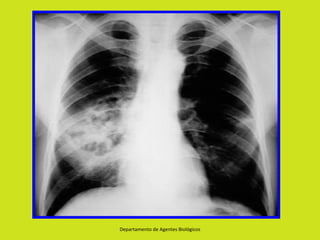

NEUMOLOGÍA

•   Neumonía necrosante

•   Neumonía de comienzo súbito

•   Neumonía en focos múltiples

•   Formación de Neumatoceles – Neumotórax

•   Empiema es complicación frecuente.

•   Neumonía Grave en menores de 12 meses.

Neumonía necrosante • Neumonía de comienzo súbito • Neumonía en focos múltiples • Formación de Neumatoceles – Neumotórax • Empiema es complicación frecuente. • Neumonía Grave en menores de 12 meses. Departamento de Agentes Biológicos